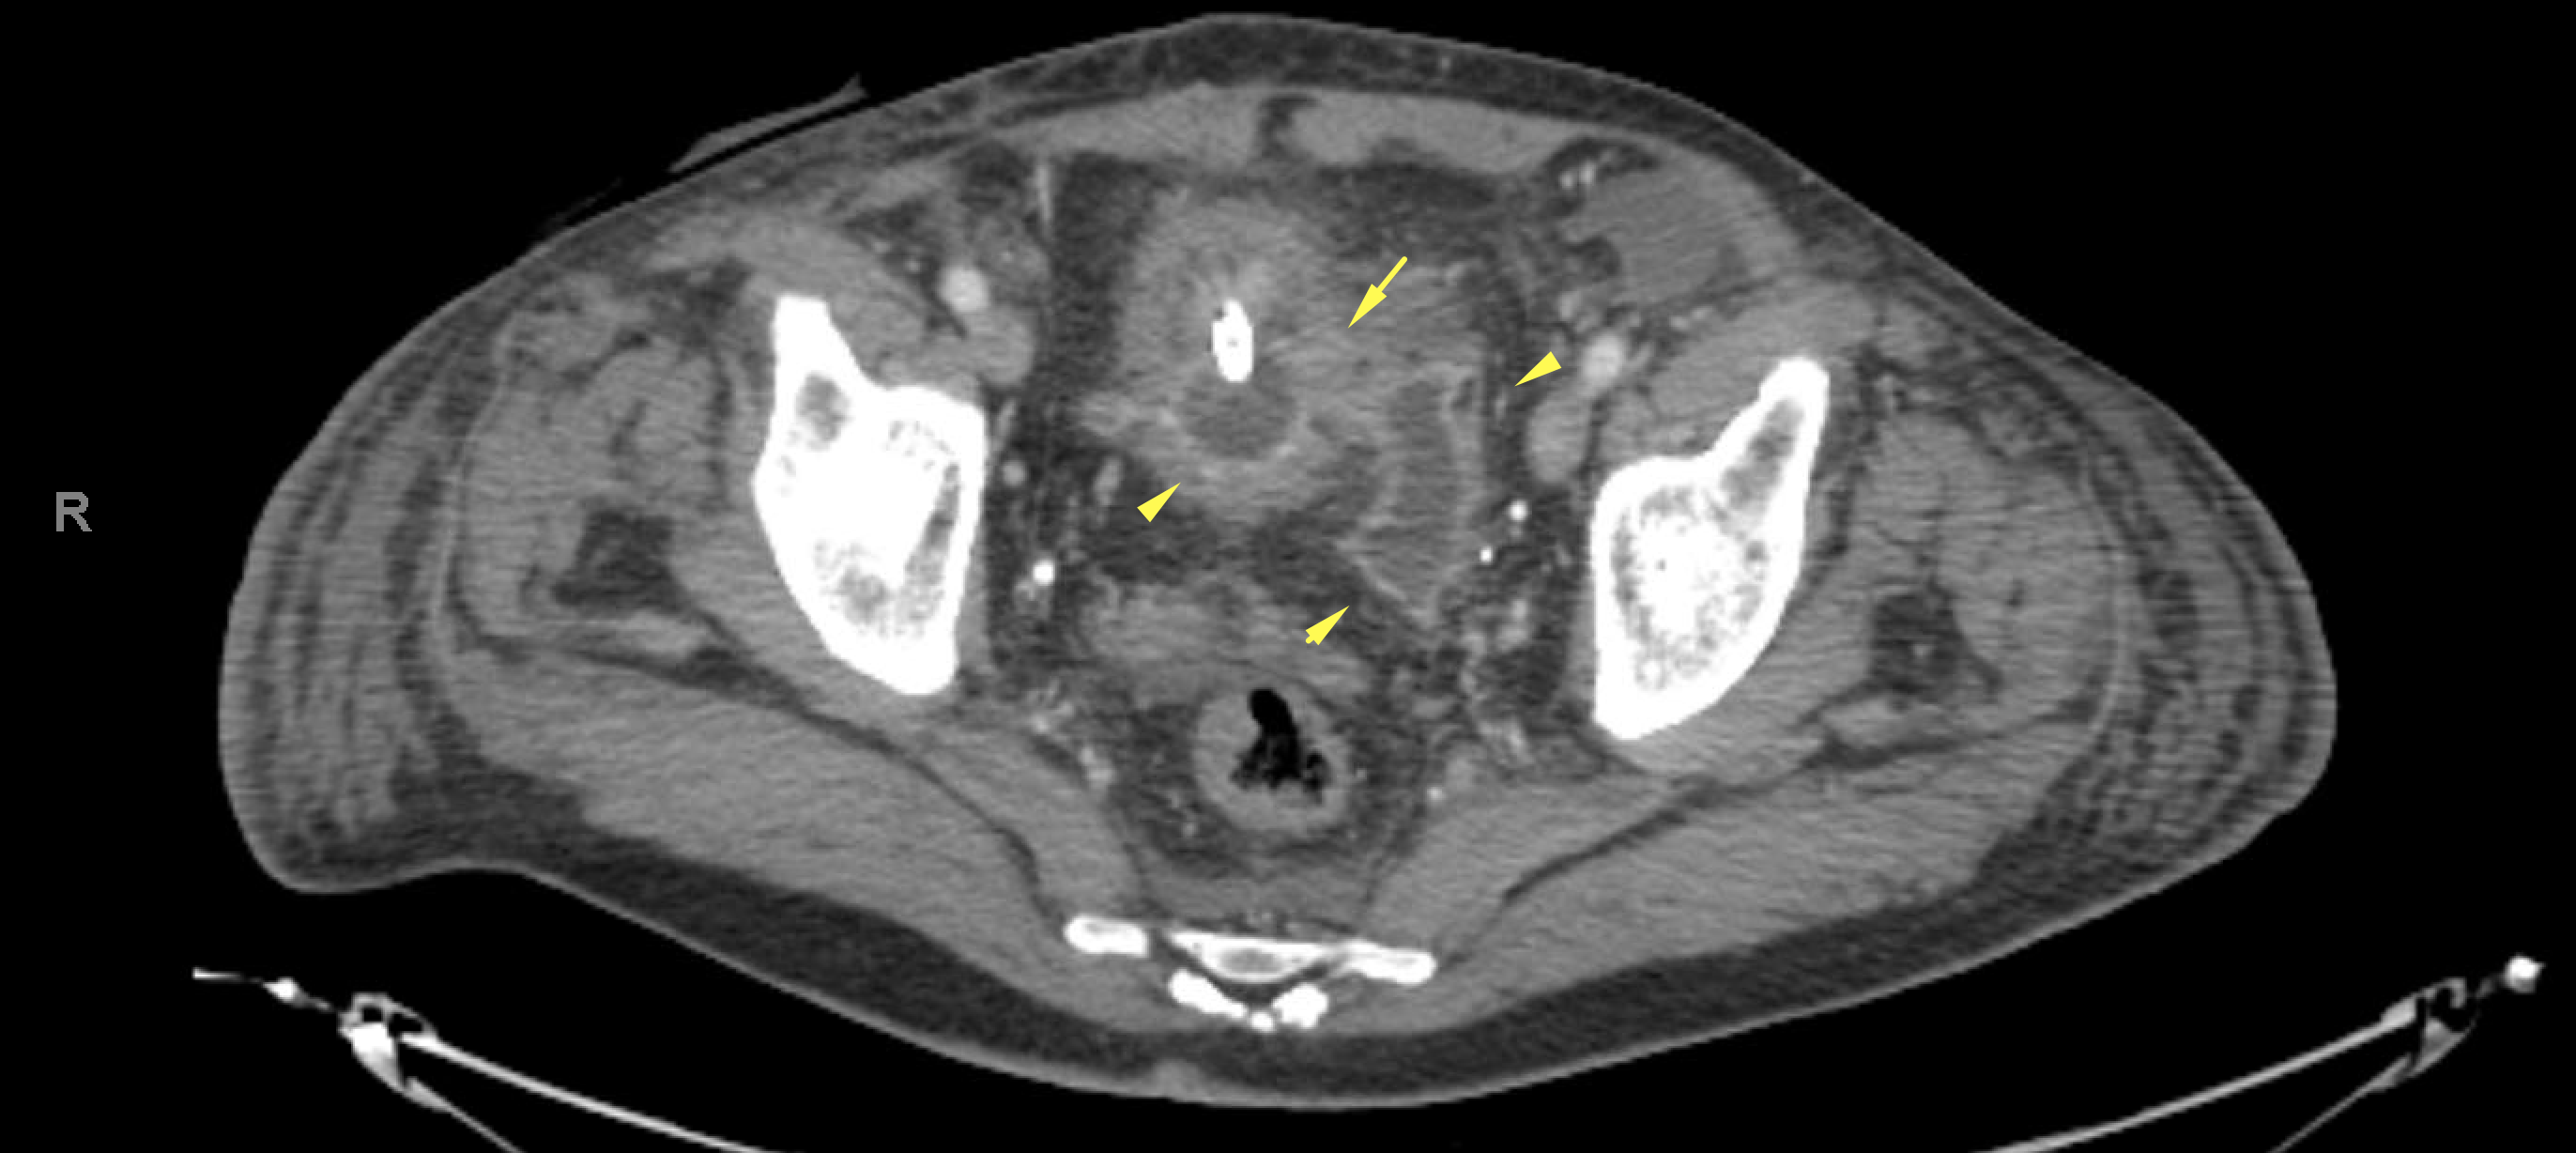

Age: 89

Sex: Male

Indication: GI bleeding

Radiotracer: Tc99m labeled RBCs

Sample ReportNo evidence of active GI bleeding during the course of this study.